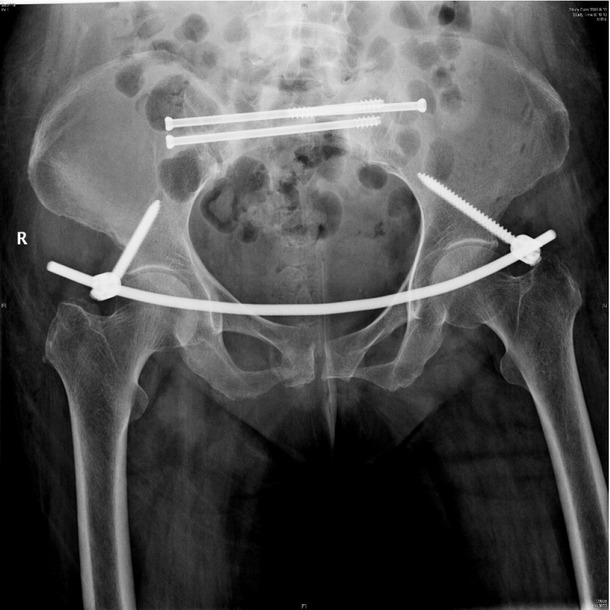

Background: Sacral insufficiency fracture (SIF)is a well defined fragility fracture but insufficient awareness of SIF currently persists among orthopedic,emergency and geriatric physicians. Objective: To heighten clinical characteristics and therapeutic principles of SIF, we presented the diagnostic and treatment process of this case. Case presentation: A 73-year old female without trauma history complained severe pain in low back and pubic symphysis for 20 days. She was diagnosed pubic fracture and lumbar spinal stenosis initially The pelvic X-ray showed mild displacement symphysis pubis fracture without dislocation of the joint (Figure 1) and Dual-energy X ray Absorptiometry (DXA) showed T score -3.2 in lumbar and-3.1in left hip. Conservative treatment,which include immobilization, multimodal pain management and osteoporosis management was carried out with limited efficacy. The patient complained sharp pain when turn over in bed. Pelvic CT was performed for further evaluation and it showed sacrum fracture in both alaes and S1 vertebral body (Figure 2). Diagnosis of insufficient sacrum fracturewas supported by CT, DXA and clinical atrauma history. Considering the prolonged pain after conservative treatment and minimal fracture displacement. Minimally invasive surgery (anterior pelvic ring internal fixator for symphysis pubis fracture combined iliosacral screws for sacrum fracture) was implemented. Visual analogue scale decreased from 8 pre-operation to 4 post operation (Figure 3). Osteoporosis management and rehabilitation was carried out postoperation. Results: The patient achieved full weight-bearing ambulation with mild pain 4 weeks postoperation and anterior pelvic ring internal fixator was moved six months postoperation (Figure 4). Conclusion: 1. Orthopedic, emergency and geriatric physicians should be vigilant against sacral insufficiency fractures in atraumatic elderly patients presenting with low back pain. 2. SIFs could be easily missed on pelvic X-ray because sacrum is poorly visualized and minimal fracture displacementof SIFs. CT and MRI is recommended for diagnosis. 3. The majority of non-displaced SIFs with low level pain could be initially treated conservatively and patients with prolonged pain could benefit significantly from osteosynthesis.

X-ray postoperation showed anterior pelvic ring internal fixator for symphysis pubis fracture combined iliosacral screws for sacrum fracture.